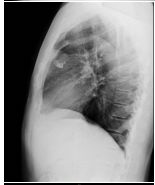

4. 39 y/o female, productive cough for 2 months